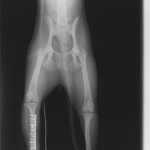

ペルシャ猫 11ヶ月齢 雄

他院にて左大腿骨遠位の成長板骨折(salter-harrisⅠ型)が認められており、治療相談を目的として来院。当院にて、キルシュナーワイヤーを用いたピンニングにより骨折部位の整復を行いました。術後の経過は良好で、現在も経過観察中です。

術後レントゲン

Arthrex社のターゲティングデバイスを用いてピンニングの位置を調整することで、確実な固定を行っています。当院ではこの手術器具以外にも、人の手術にも使用される様々な器具を導入し、手術精度を高め、また医療メーカーと新しい器具の開発、試作にも取り組んでおります。